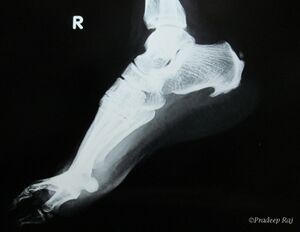

صورة بالأشعة توضح نبتة عظمية على الجوانب الخلفية والسفلية من العقب | |

مهماز العقب (إنگليزية: calcaneal spur، يُعرف أيضاً باسم مهماز الكعب إنگليزية: heel spur)، هو نتوء عظمي ينمو من عظام الكعب.[1] عادة ما يكتشف مهماز العقب بالأشعة السينية.[2] وهو يشكل العرن.

يمكن الكشف عن مهماز العقب بالفحص البدني متبعاً بإجراء الأشعة السينية جانبية للقدم.[بحاجة لمصدر]